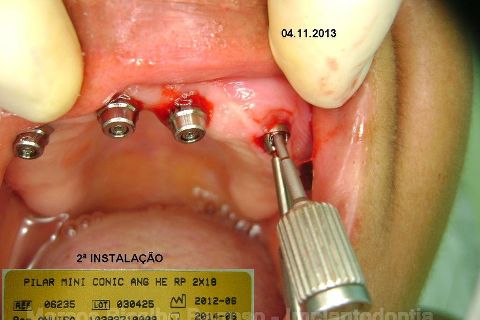

Atualização do caso clínico que já postei, "REABILITAÇÃO EM MAXILA ATRÓFICA COM IMPLANTES", um caso que inclui expansão do rebordo estreito com cinzel e martelo, expansores rosqueáveis, enxerto e instalação dos implantes distais inclinados tangenciando seio maxilar. Inclui esvaziamento do forame nasopalatino e preenchimento com biomaterial para instalação de dois implantes próximos dele. Cirurgia realizada em única sessão, com instalação dos 6 implantes. Para os colegas que não conheceram e/ou esqueceram da apresentação, este é o resumo do caso na fase cirúrgica.http://www.youtube.com/watch?v=BtvexFexRPA&hd=1

FASE PROTÉTICA DA REABILITAÇÃO EM MAXILA ATRÓFICA...incluindo a reabertura, instalação dos minipilares e PTR provisória reembasada sobre os cilindros de proteção.